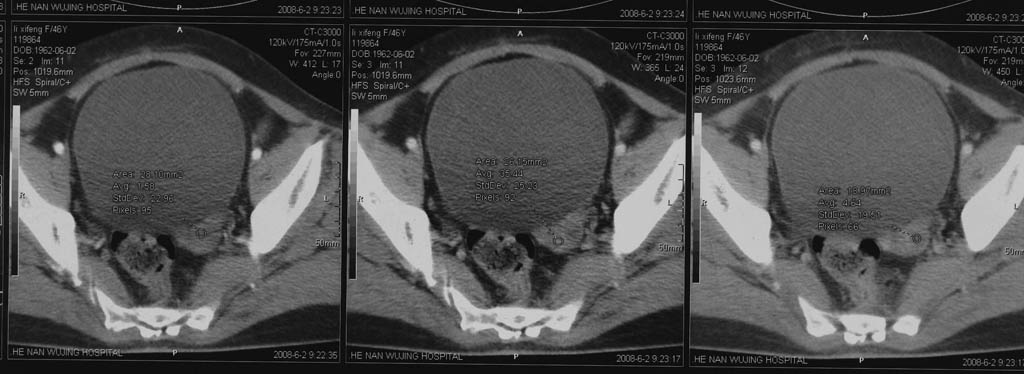

5年前子宫肌瘤 子宫切除,2年前整个下腹痛2周余病因不名,2008年5月底再次左下腹痛行ct,6月2日ct增强,请指教

后面的图像就是增强的啊,包块下部还有细小的钙化点